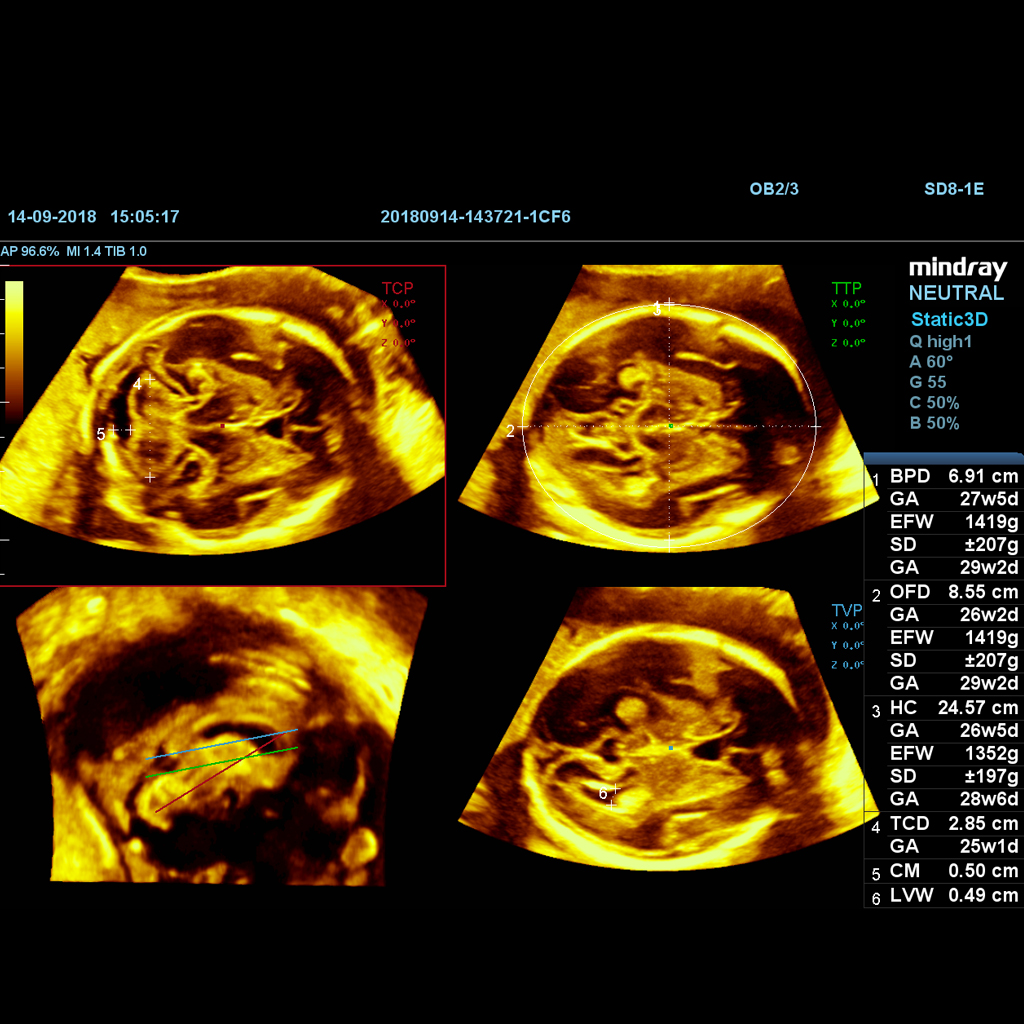

Компютърно решение за изследване на мозъка на плода. Smart Planes предоставя удобен за потребителя инструмент, който значително подобрява ефективността на сканирането чрез повишена точност, съчетана с автоматизирана работа.